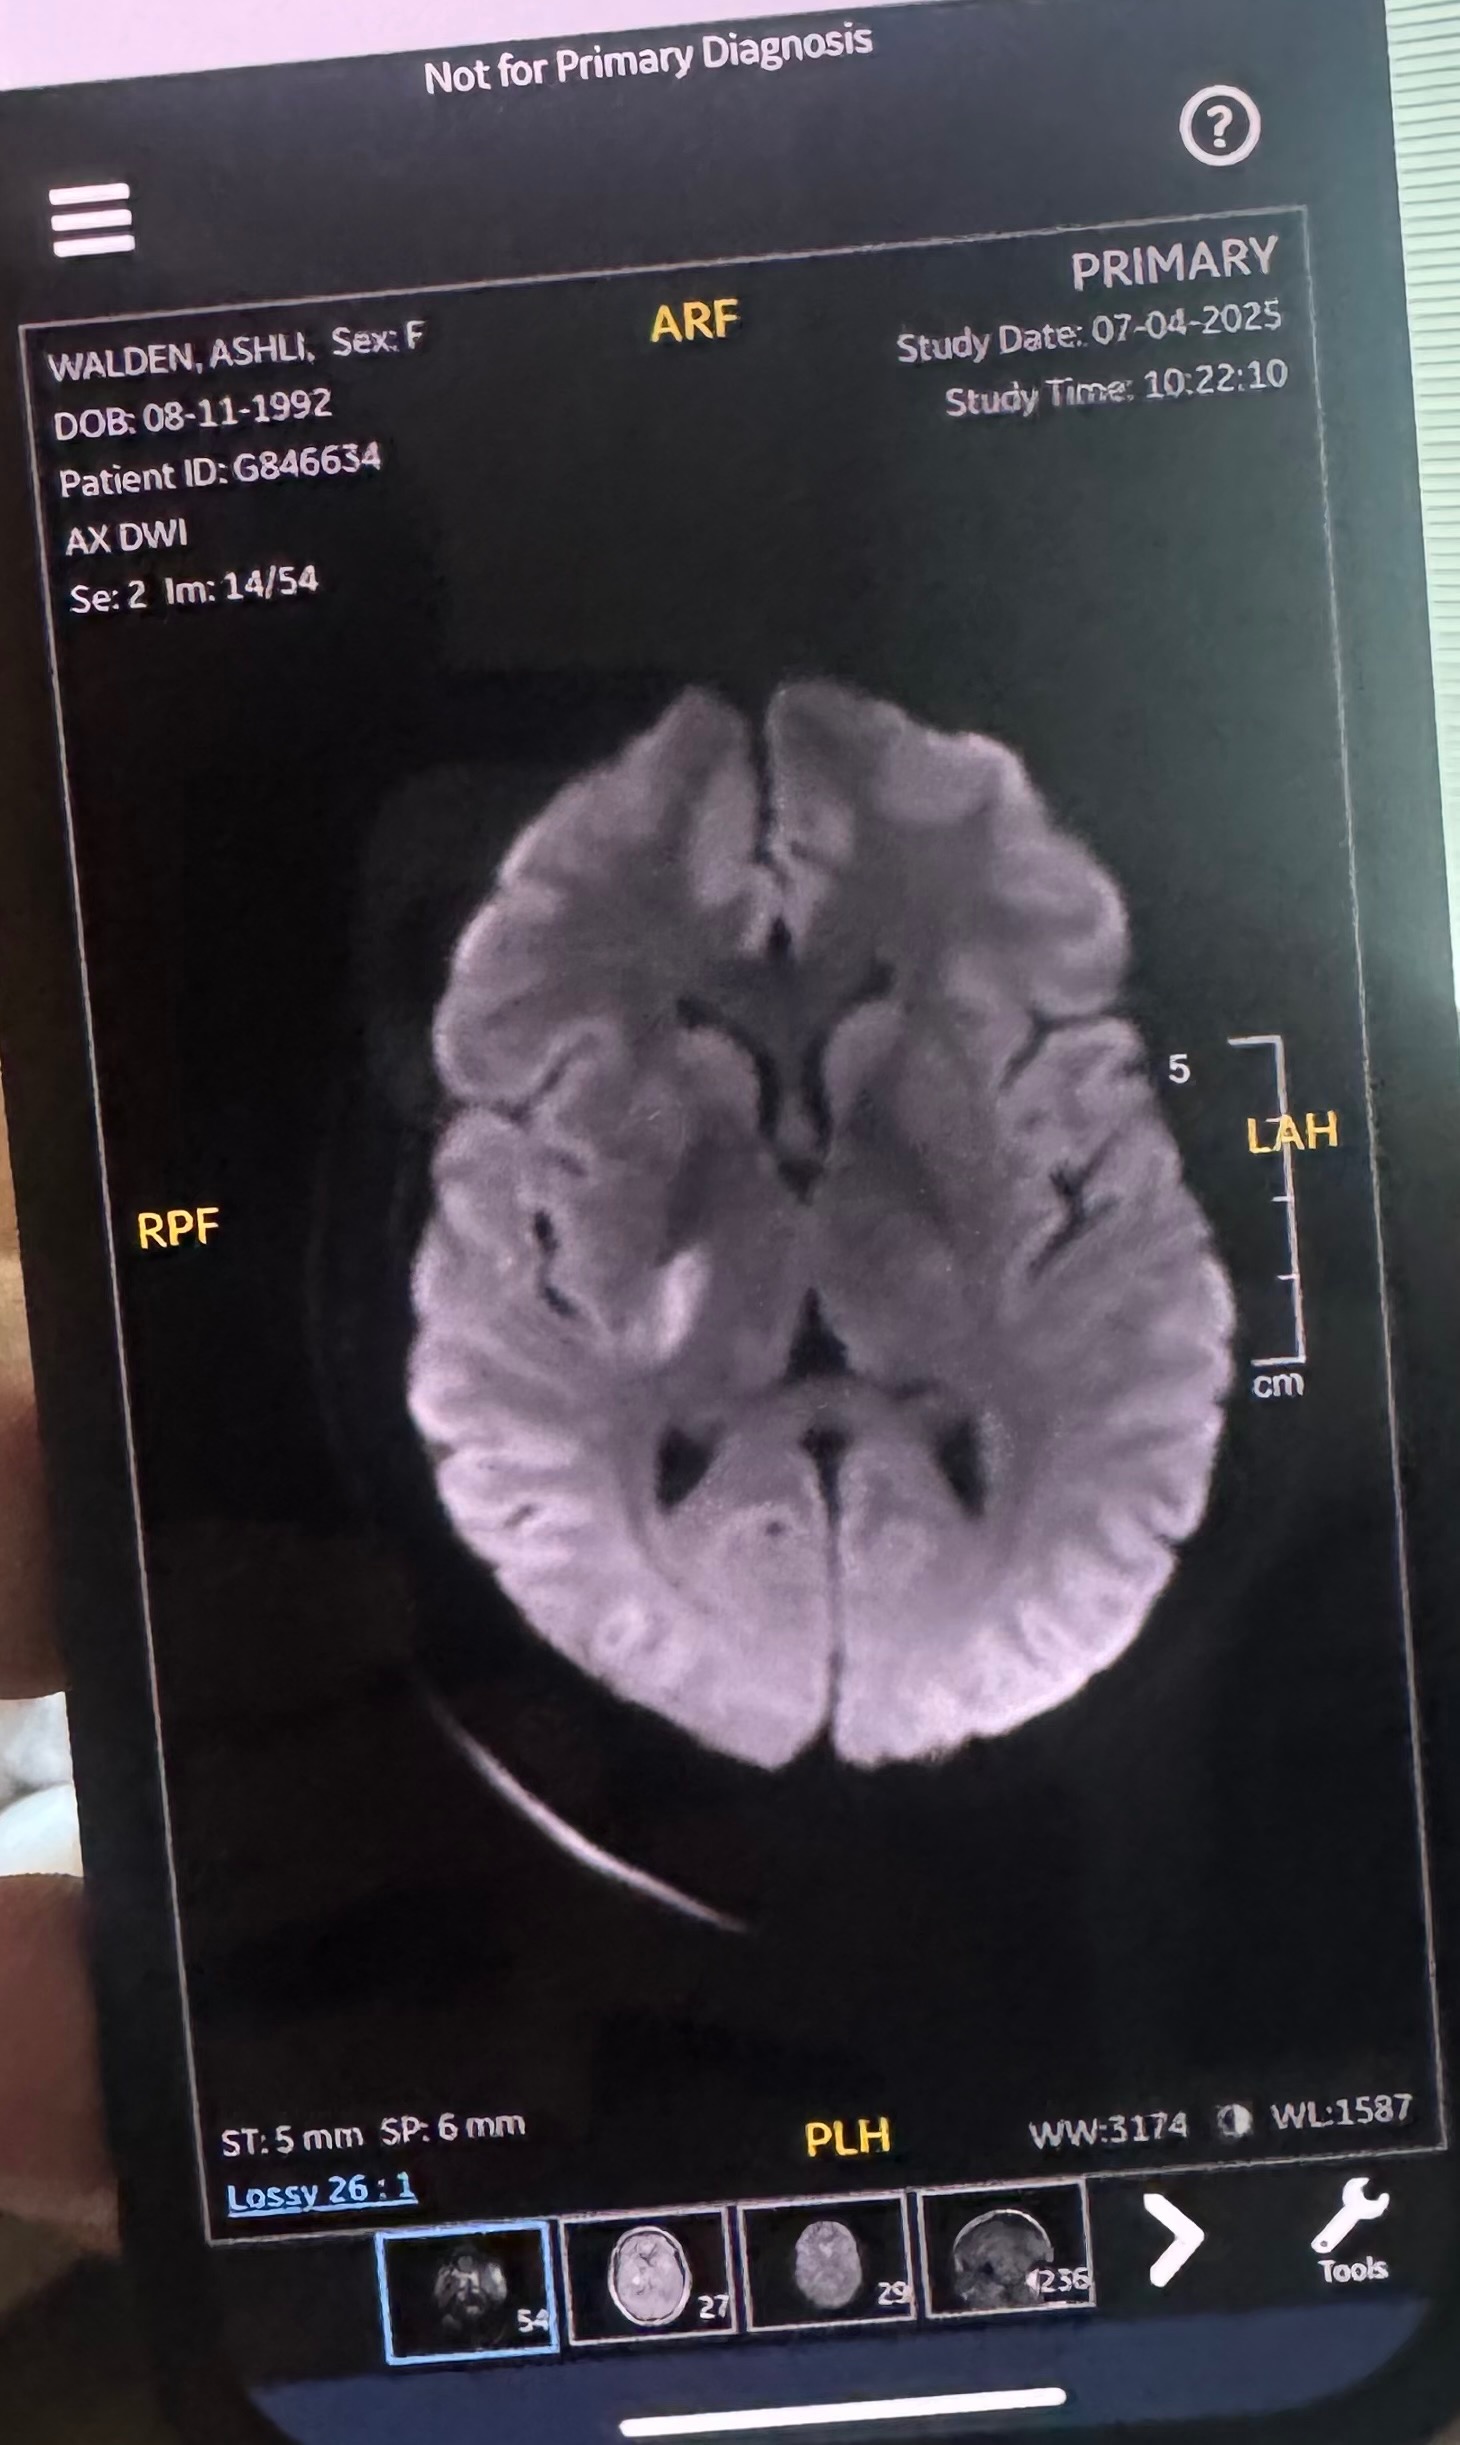

- This stroke has affected her right basal ganglia. A stroke in the right basal ganglia can cause a range of neurological issues, including movement disorders, emotional and cognitive impairments, and difficulties with spatial awareness and perception. Specifically, damage to the right basal ganglia can lead to left-sided neglect, making it difficult to recognize or respond to stimuli on the left side of the body and environment. Other potential effects include apathy, slowed or reduced movement, memory problems, and emotional blunting. Physical therapy will be required to gain strength back in her left side. This has also had an impact on cognition. She’s currently unable to fully read or understand text messages and struggles to form a response back via text. She is able to understand physical language, so a phone call or video call is best right now.